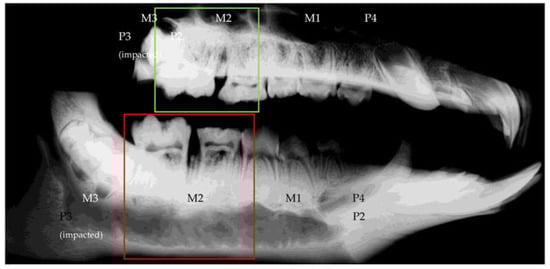

3.1. Success of the Periodontitis Induction Protocol

3.2.3. Radiological Evaluation